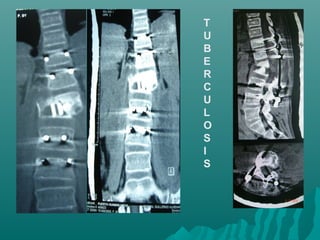

TEM DE COLUMNATEM DE COLUMNA

VERTEBRALVERTEBRAL

Protocolo para columnaProtocolo para columna

 INDICACIONES:INDICACIONES:

 MODO ESPIRAL PARA ESTUDIOS DEMODO ESPIRAL PARA ESTUDIOS DE

COLUMNA V.G. CAMBIOS POSTCOLUMNA V.G. CAMBIOS POST

TRAUMATICOS, TUMORES,TRAUMATICOS, TUMORES,

MALFORMACIONES O INDICACIONESMALFORMACIONES O INDICACIONES

ORTOPEDICA, ETC.ORTOPEDICA, ETC.

 UNA DISTANCIA DE 15 CM. SEUNA DISTANCIA DE 15 CM. SE

CUBRIRA EN 14.5 SEGUNDOSCUBRIRA EN 14.5 SEGUNDOS

T

U

B

E

R

C

L

O

S

I